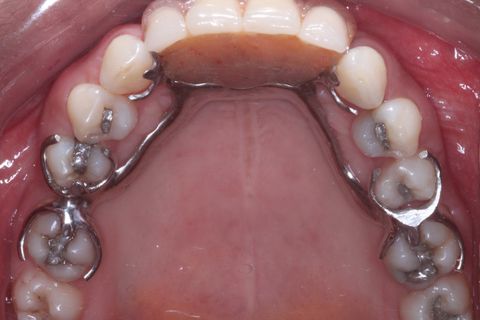

Foto oclusal superior

Foto Oclusal superior sem a Prótese Parcial removível

Paciente do sexo feminino, 32 anos e 10 mêses de idade, com ausência dos incisivos centrais e laterais superiores, associado a um defeito ósseo vestibular côncavo. Realizamos planejamento reverso, ou seja, enceramento diganóstico prévio para avaliação do defeito ósseo em termos de quantidade e do posicionamento final das próteses. A paciente foi submetido a um enxerto ósseo autógeno do ramo ascendente lado direito e fixação dos blocos ósseos na área receptora, com fixação dos mesmos através de parafusos de fixação com cabeça expandida Neodent. Após 6 meses foram instalados 4 implantes Neodent.